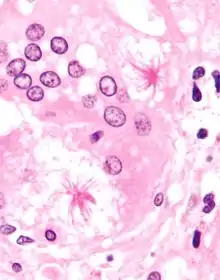

Macrophages (specifically histiocytes) are the cells that define a granuloma. They often fuse to form multinucleated giant cells (Langhans giant cell).[7] The macrophages in granulomas are often referred to as "epithelioid". This term refers to the vague resemblance of these macrophages to epithelial cells. Epithelioid macrophages differ from ordinary macrophages in that they have elongated nuclei that often resemble the sole of a slipper or shoe. They also have larger nuclei than ordinary macrophages, and their cytoplasm is typically pinker when stained with eosin. These changes are thought to be a consequence of "activation" of the macrophage by the offending antigen.